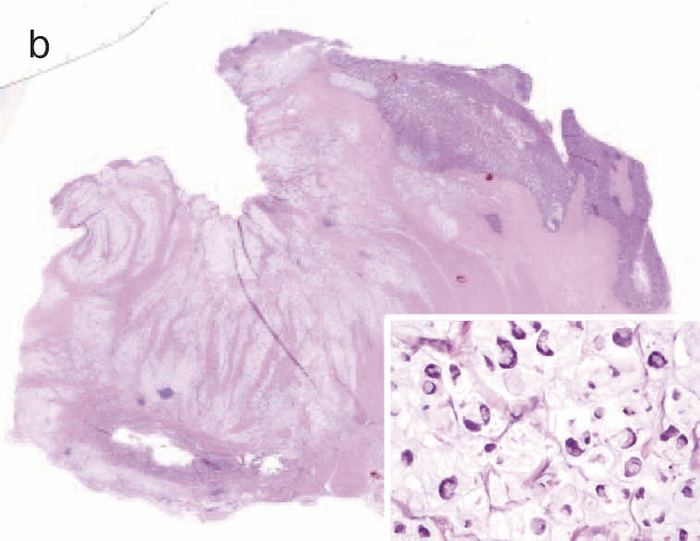

図28 CD関連進行直腸・肛門管癌(5型)の代表的な肉眼像・組織像

1. 肉眼像:直腸・肛門管部に内腔狭窄を伴った5型腫瘍(矢印)を認める。

2. 組織像(HE染色):組織学的には,壁内に浸潤している粘液癌を認める(inset:粘液癌の拡大像)。